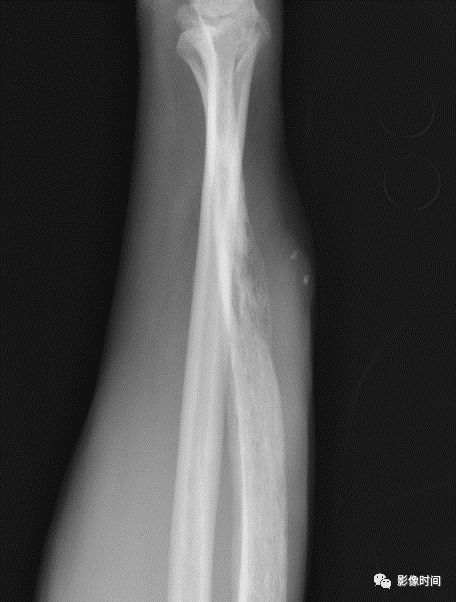

(一)地图样破坏  地图样破坏是指肿瘤组织在一个局部呈团块状生长造成界限清楚的骨质破坏(图 1、图 2、图 3、图 4)。

病灶可位于骨的中心或一侧部位,呈圆形、卵圆形密度减低区,与正常骨质分界清晰,边缘可有或无硬化带围绕,骨的形态无变化,病灶内可完全透亮或可见粗细不均、大小不等的残留骨嵴,内缘可光滑或呈分叶状压迹。

地图样破坏见于大多数良性肿瘤和肿瘤样病变如单纯性骨囊肿、骨纤维结构不良、血管瘤等、也可见于部分恶性骨肿瘤如骨转移瘤、骨髓瘤等。

图 1  地图样破坏:单纯性骨囊肿